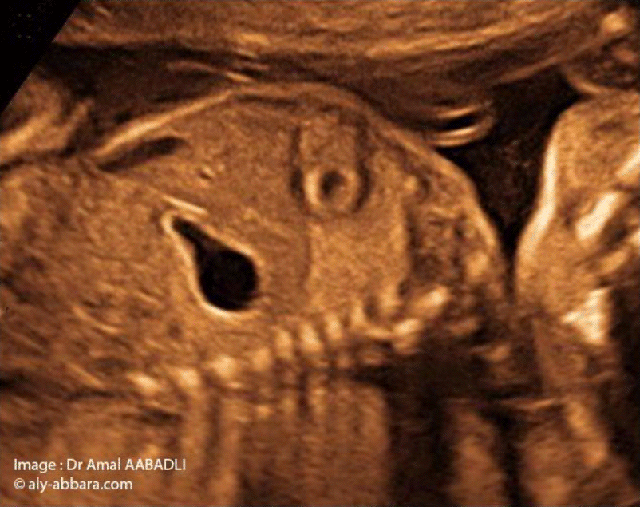

من بين الصور الضرورية و الأولية لفحص الجنين توجد صورة الحجاب الحاجز التي تظهر القلب و الرئة من جهة و المعدة من جهة ثانية و يفصل بينهم الحجاب الحاجز.

هذه الصورة مهمة جداً لنفي حالات فتف الحجاب الحاجز و لا يمكن أن يتم فحص الجنين في الثلاثية الثانية من الحمل دون تدوين هذه الصورة شأنها شأن صور الرأس و البطن

هذه الصورة سهلة المنال و يحصل عليها بقطعة طولية سهمية للجنين مائلة إلى اليسار حيث توجد المعدة.

• Parmi les images nécessaires lors de la réalisation d'une exploration échographique fœtale, c'est l'image sur laquelle on met en évidence le cœur et le poumon d'un côté, puis l'estomac de l'autre côté, avec le diaphragme séparant ces deux côtés de l'image.

• Il s'agit d'une image nécessaire permettant d'éliminer la présence d'une hernie diaphragmatique ; il ne faut pas qu'une exploration échographique fœtale soit réalisée au cours du deuxième trimestre de la grossesse, sans produire cette image comme c'est le cas pour la coupe de la tête et le ventre fœtaux.

• Cette icône échographique est facile à obtenir en réalisant une coupe sagittale sur le tronc fœtal déviée vers la gauche.